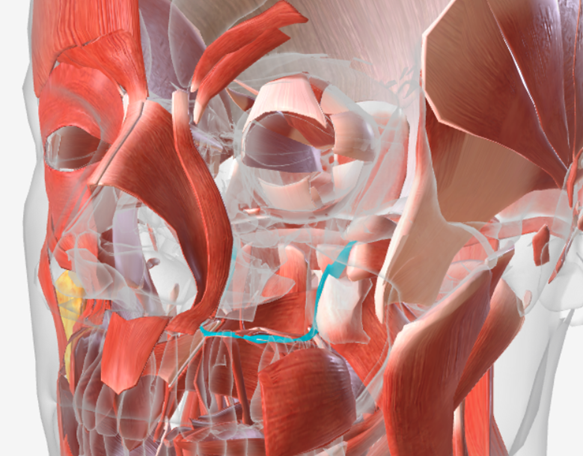

Superior pharyngeal constrictor

origin is on the pterygomandibular raphe, coursing posteriorly to insert on the median raphe of the pharyngeal aponeurosis function is to pull the pharyngeal wall forward to constrict the pharyngeal diameter

Middle pharyngeal constrictor

origin is on the horns of the hyoid and stylohyoid ligament, coursing up and back to the median pharyngeal raphe; function is to narrow the diameter of the pharynx

Inferior pharyngeal constrictor

origin is the oblique line of the thyroid laminae, coursing up and back to insert on the median pharyngeal raphe; function is to reduce the diameter of the lower pharynx

Cricopharyngeus

origin is the cricoid cartilage, coursing back to the orifice of the esophagus; function is to constrict the superior orifice of the esophagus; also referred to as the upper esophageal sphincter

Salpingopharyngeus

origin is the lower margin of the auditory tube, coursing down to insert into the palatopharyngeus muscle; function is to elevate the lateral pharyngeal wall

Stylopharyngeus

origin is the styloid process, coursing down to insert into the pharyngeal constrictors and the posterior thyroid cartilage; function is to elevate and open the pharynx

Superior Pharyngeal Constrictor

|  |  |

Middle Pharyngeal Constrictor

|  |  |

Inferior Pharyngeal Constrictor

|  |  |

Cricopharyngeus

|  |  |

Saplingopharyngeus

|  |  |

Stylopharyngeus

|  |  |